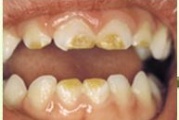

Fluoroos

Fluoroosi